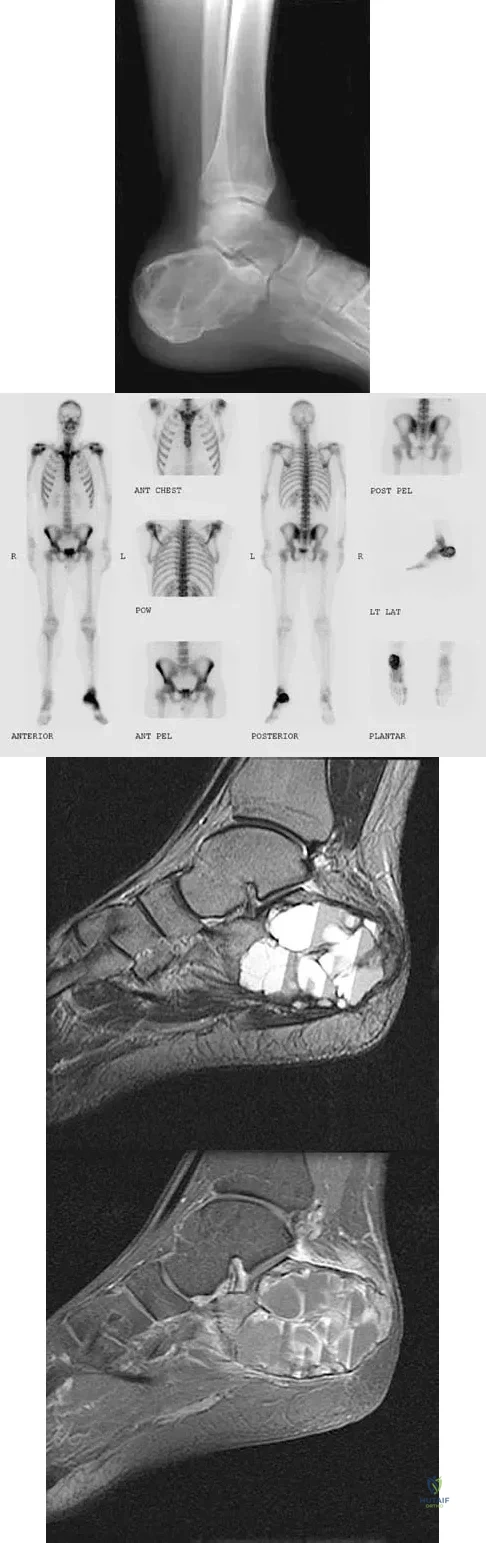

A 23-year-old man has had heel pain and fullness for the past several months. He reports that initially the pain was present only with activity, but more recently the pain has become constant. Figures 53a through 53d show a radiograph, a bone scan, and T2-weighted and gadolinium MRI scans. What is the most likely diagnosis?

Explanation